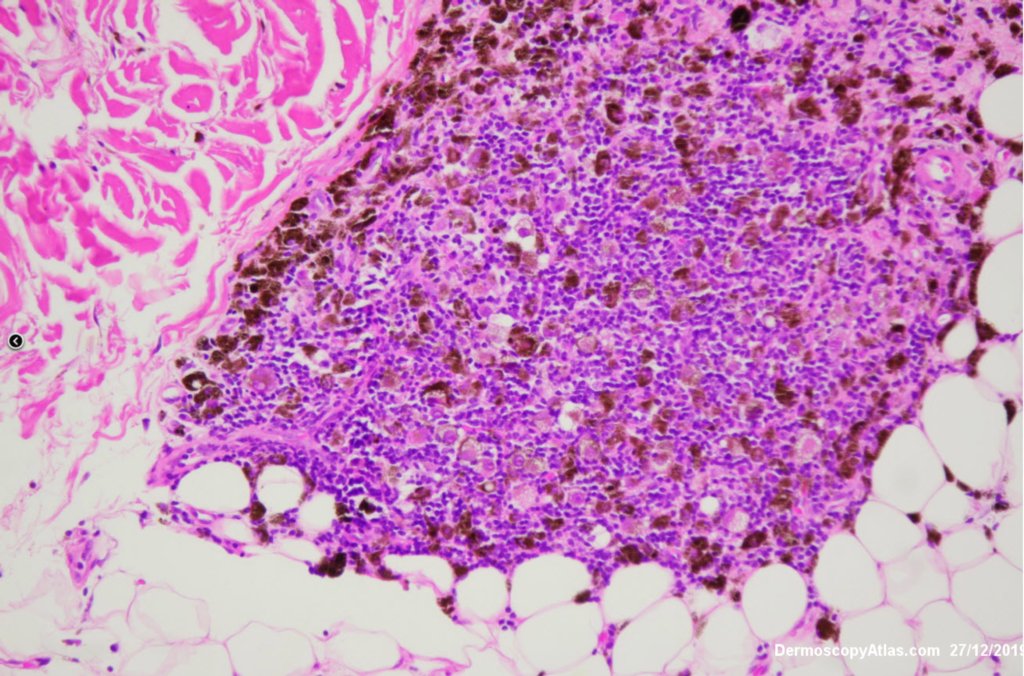

Site: Cheek

Diagnosis: Melanoma metastases

Description: Background brown lesion with blue macules and papules developing

This elderly man had a preceeding lentigo maligna but subsequently developed in transit metastases as shown by the blue macules and papules on his cheek. He was treated with Keytruda. PET scan was negative for spread elsewhere.

It is important to treat lentigo maligna early to stop a situation like this from developing.